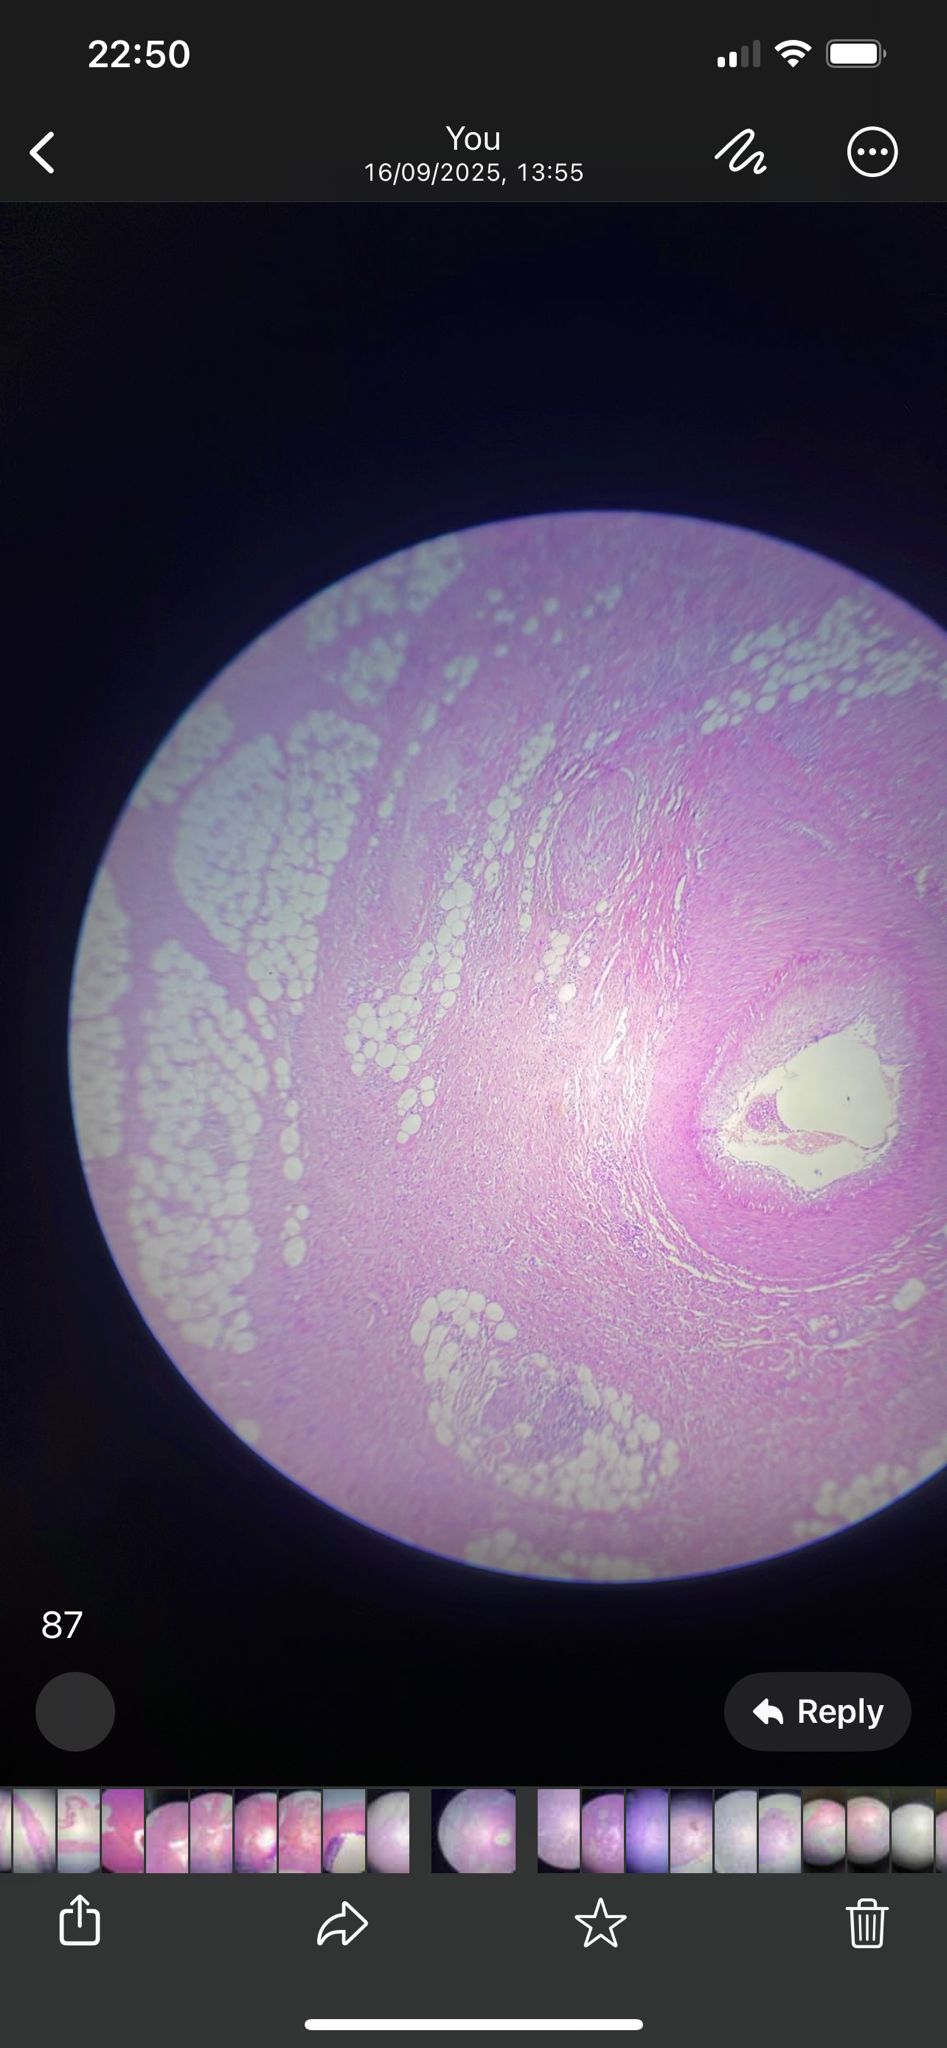

Micronodular cirrhosis of the liver. (pycrofuxin by van Gieson method stain)